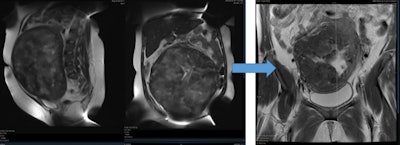

Uterine fibroid embolization blocks blood supply to treat painful uterine fibroids, and the procedure has a comparable fertility rate to myomectomy for women who want to conceive, according to what is thought to be the first study on the subject in the Middle East. The study was conducted by our group at Al Ain Hospital and presented ahead of print at the 2016 Arab Health Conference in Dubai, United Arab Emirates, in January and also presented at the Abu Dhabi annual gynecology conference in October 2015 and the Cleveland Clinic Abu Dhabi radiology conference in November 2015.

In a retrospective chart review of patients younger than the age of 40 (35 patients) who wished to spare their fertility and underwent UFE from 2011 to 2016, 18 patients reported 23 pregnancies, of which five were miscarriages. Two more pregnancies were complicated by premature labor. Of the 23 pregnancies, 16 were normal full-term pregnancies, 15 women had become pregnant once, and four had become pregnant twice.

Our group of 23 pregnancies was small, but did confirm successful pregnancy after UFE. The 45.7% pregnancy rate in women younger than 40 years old who achieved a term pregnancy compares favorably with women who underwent myomectomy via a number of techniques. Of the women in the cohort who did conceive, subsequent birth proceeded normally (86%).